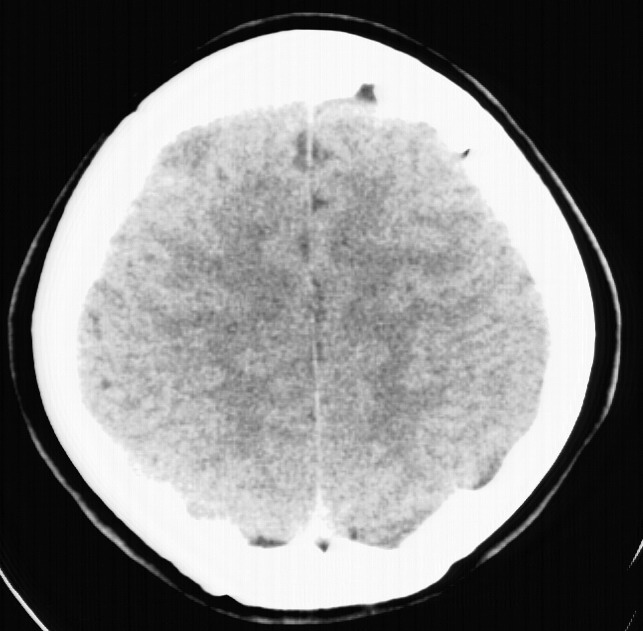

标题: CT5853:右额叶上部占位请会诊

女,34岁,自述头晕胀2年,近期感精神恍惚,无发热,实验室检查阴性。

右额叶低密度灶,脑回分离,无水肿及强化,考虑脑脓肿,建议mri检查

右顶叶靠近脑表面圆形低密度灶,周围无水肿及占位效应,增强病灶无明显强化,考虑:右顶叶低分级星型细胞瘤。

病灶没有明显的强化,支持囊性星形细胞瘤!不过它的形态倒是比较象肉芽肿的,还是做个mri检查吧

支持囊性星形细胞瘤!还是做个mri检查排除其它病变。